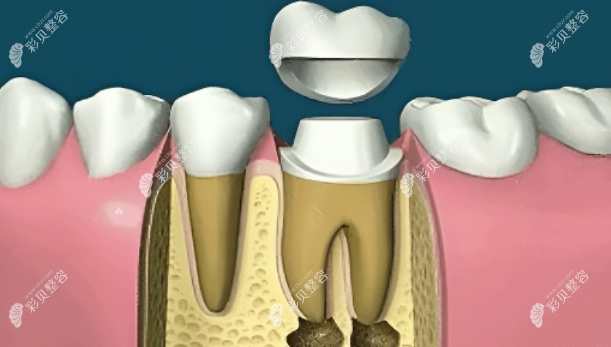

7、根管打桩

根管打桩的目的就是为了增强牙齿的固位能力彩。贝网

一般常用纤维桩和金属桩,有点像树苗下面的根和包裹的泥土一样,能加固和延长牙齿,具有比较好的稳定性。

8、完成牙体修复

做完根管治疗后,医生一般会建议重新做一个牙冠,这样能更有效的保护牙齿,减少剩余牙冠部分容易折断劈裂的可能性,增加牙齿使用寿命。